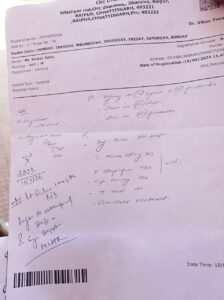

रायपुर,सिलयारी। स्थानीय वार्ड 19 साहू पारा में एक गरीब युवक के साथ अभद्र गाली गलौज व जान से मारने की धमकी देते हुए मारपीट करने का मामला प्रकाश में आया है। मारपीट से युवक गंभीर रुप से घायल हो गया और उसके आंखों से खून रिसने लगा। उसके बावजूद धरसींवा पुलिस द्वारा मुलायजा न कराया जाना कई प्रकार के संदेहों को जन्म देता है।

प्राप्त जानकारी के अनुसार साहू पारा सिलयारी निवासी विक्की साहू पिता स्व शंकर साहू ट्रेन में घुम-घुमकर चना बेचकर अपने परिवार का लालन-पालन करता है। गत 17 सितंबर को गणेश विसर्जन में शामिल होने गया था। दोपहर 2 बजे उसके पड़ोसियों ने बताया कि सुनील साहू अपने साथियों के साथ गाली गलौज कर रहा है। यह सुनते ही जब वहां पहुंचकर गाली गलौज क्यों कर रहे हो कहां तो वह मेरे साथ गाली गलौज करने लगे। इसे सुनकर सुनील साहू की मां ने भी विरोध किया तब वें शांत हुए। विक्की साहू के अनुसार शाम को सात बजे सुनील साहू, ओमू साहू, पोषण साहू व एक अन्य ने मेरे साथ मारपीट करने लगे। इससे उसे काफी घोंटें पहुंची और आंखों से खून बहने लगा। इसकी रिपोर्ट सिलयारी पुलिस चौकी में लिखवाने पहुंचा जिसे धरसीवां पुलिस थाना में स्थानांतरित किया गया। पुलिस ने भादंवि की धारा 296,115/2/, 352/2/, 3/5/ के तहत मामला दर्ज कर खानापूर्ति करने की बातें सामने आ रही है।